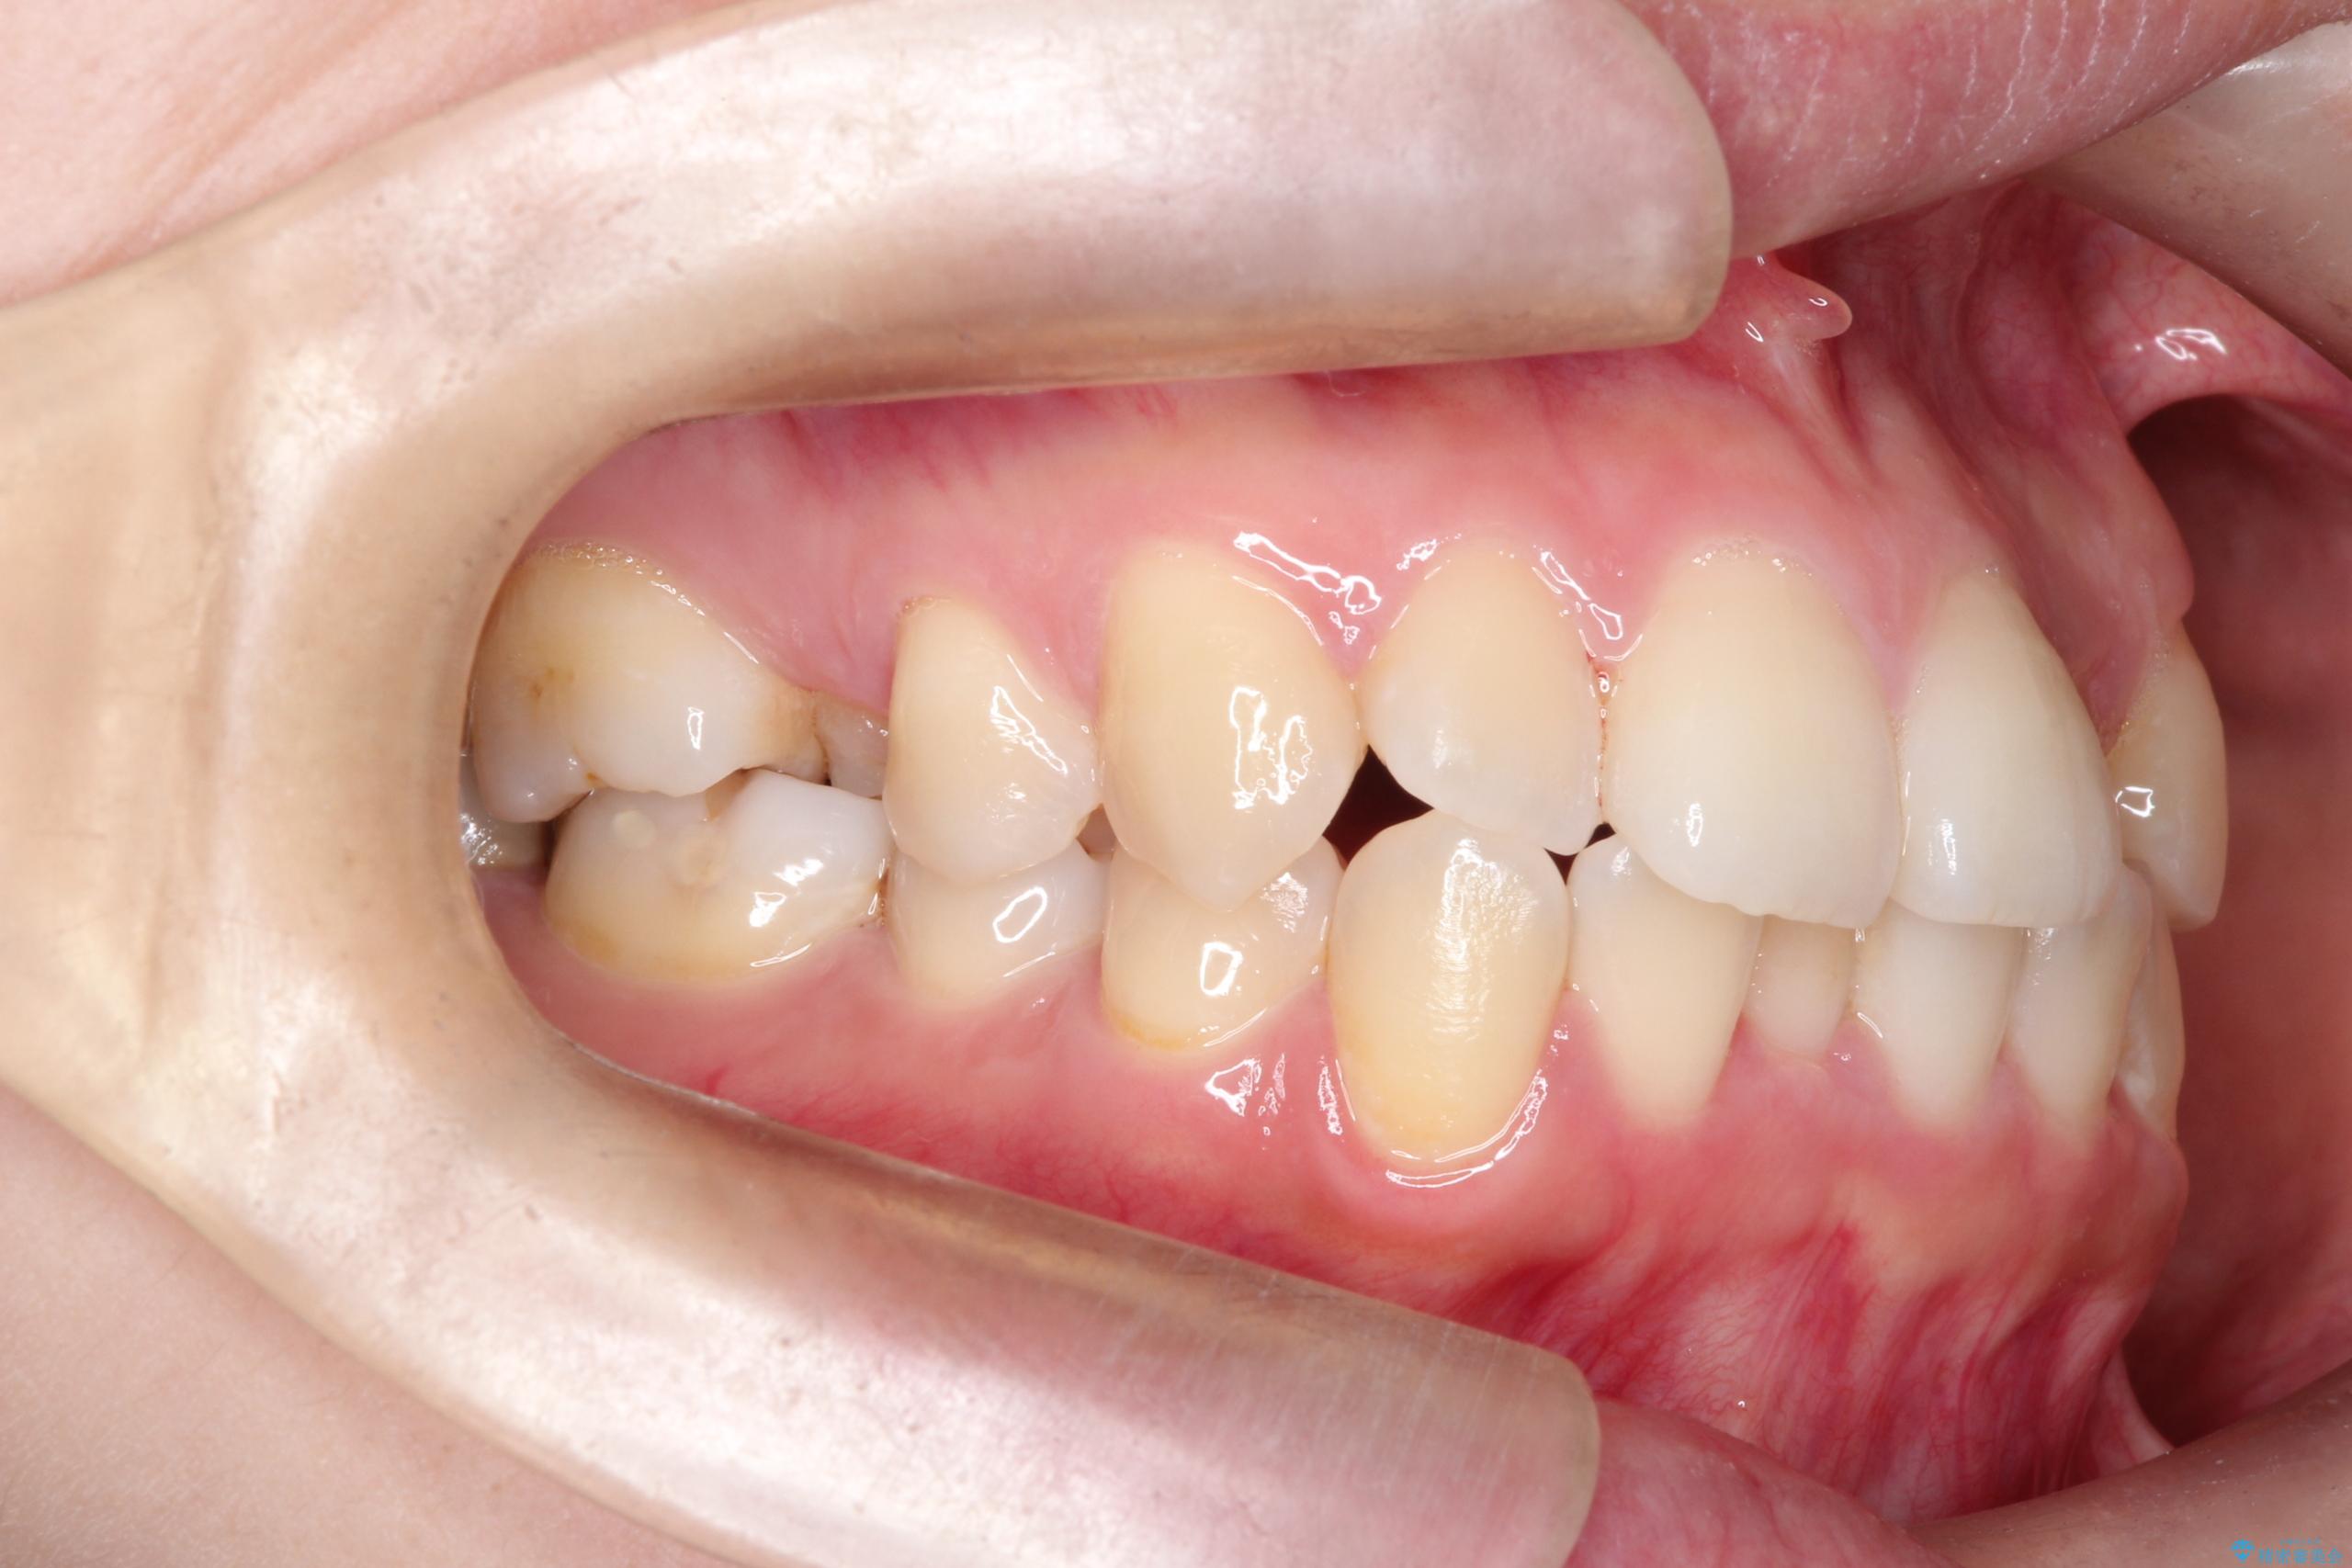

- 主訴:口元を下げて前突感を無くしたい、下の歯の凹凸も無くしたい

骨格的顎の変位を認めたため、顔貌に対しピッタリ上下の歯の正中を合わせることは難しいと説明し、上下左右計4本小臼歯を抜歯しワイヤー矯正治療を行いました。